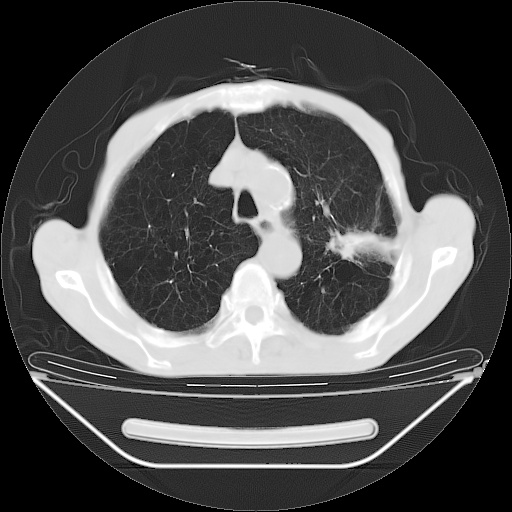

以下是引用zsl6918在2008-8-25 21:55:00的发言:[br]符合右肺周围性肺癌并肺内转移,左肺结核球。双肺肺气肿。腰椎附件转移。

以下是引用随光逐影在2008-8-25 22:03:00的发言:[br]1)考虑右肺下叶周围性肺癌并肺内转移,腰椎附件转移。2)左上肺结核(结核球形成)。3)双肺肺气肿(多发肺大泡形成)。4)双肺门区及纵隔内多发淋巴结钙化。